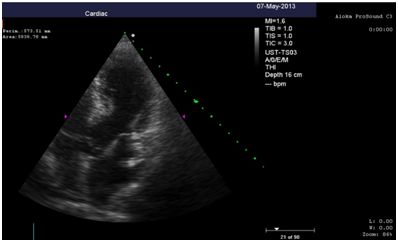

Repeated echocardiography revealed the zone of violation of local contractility (akinesis and pronounced hypokinesis) all segments on the medial and apical level with the formation of acute left ventricular aneurysm, a marked reduction of EF (23%), hyperkinesis all segments at the basal level (Figure 4-8). Troponin test was strongly positive (Figure 9). The patient is re-examined by a cardiologist, on the basis of ECG, Echo pattern, and the presence of markers of myocardial damage diagnosed with acute myocardial infarction in type 2 complicated by development of acute left ventricular aneurysm, acute heart failure Killip class IV. We carried out differential diagnosis between stress cardiomyopathy and myocarditis.

Figure 5 Echocardiography: 2АС, hyperkinesis of the basal segments with apical ballooning